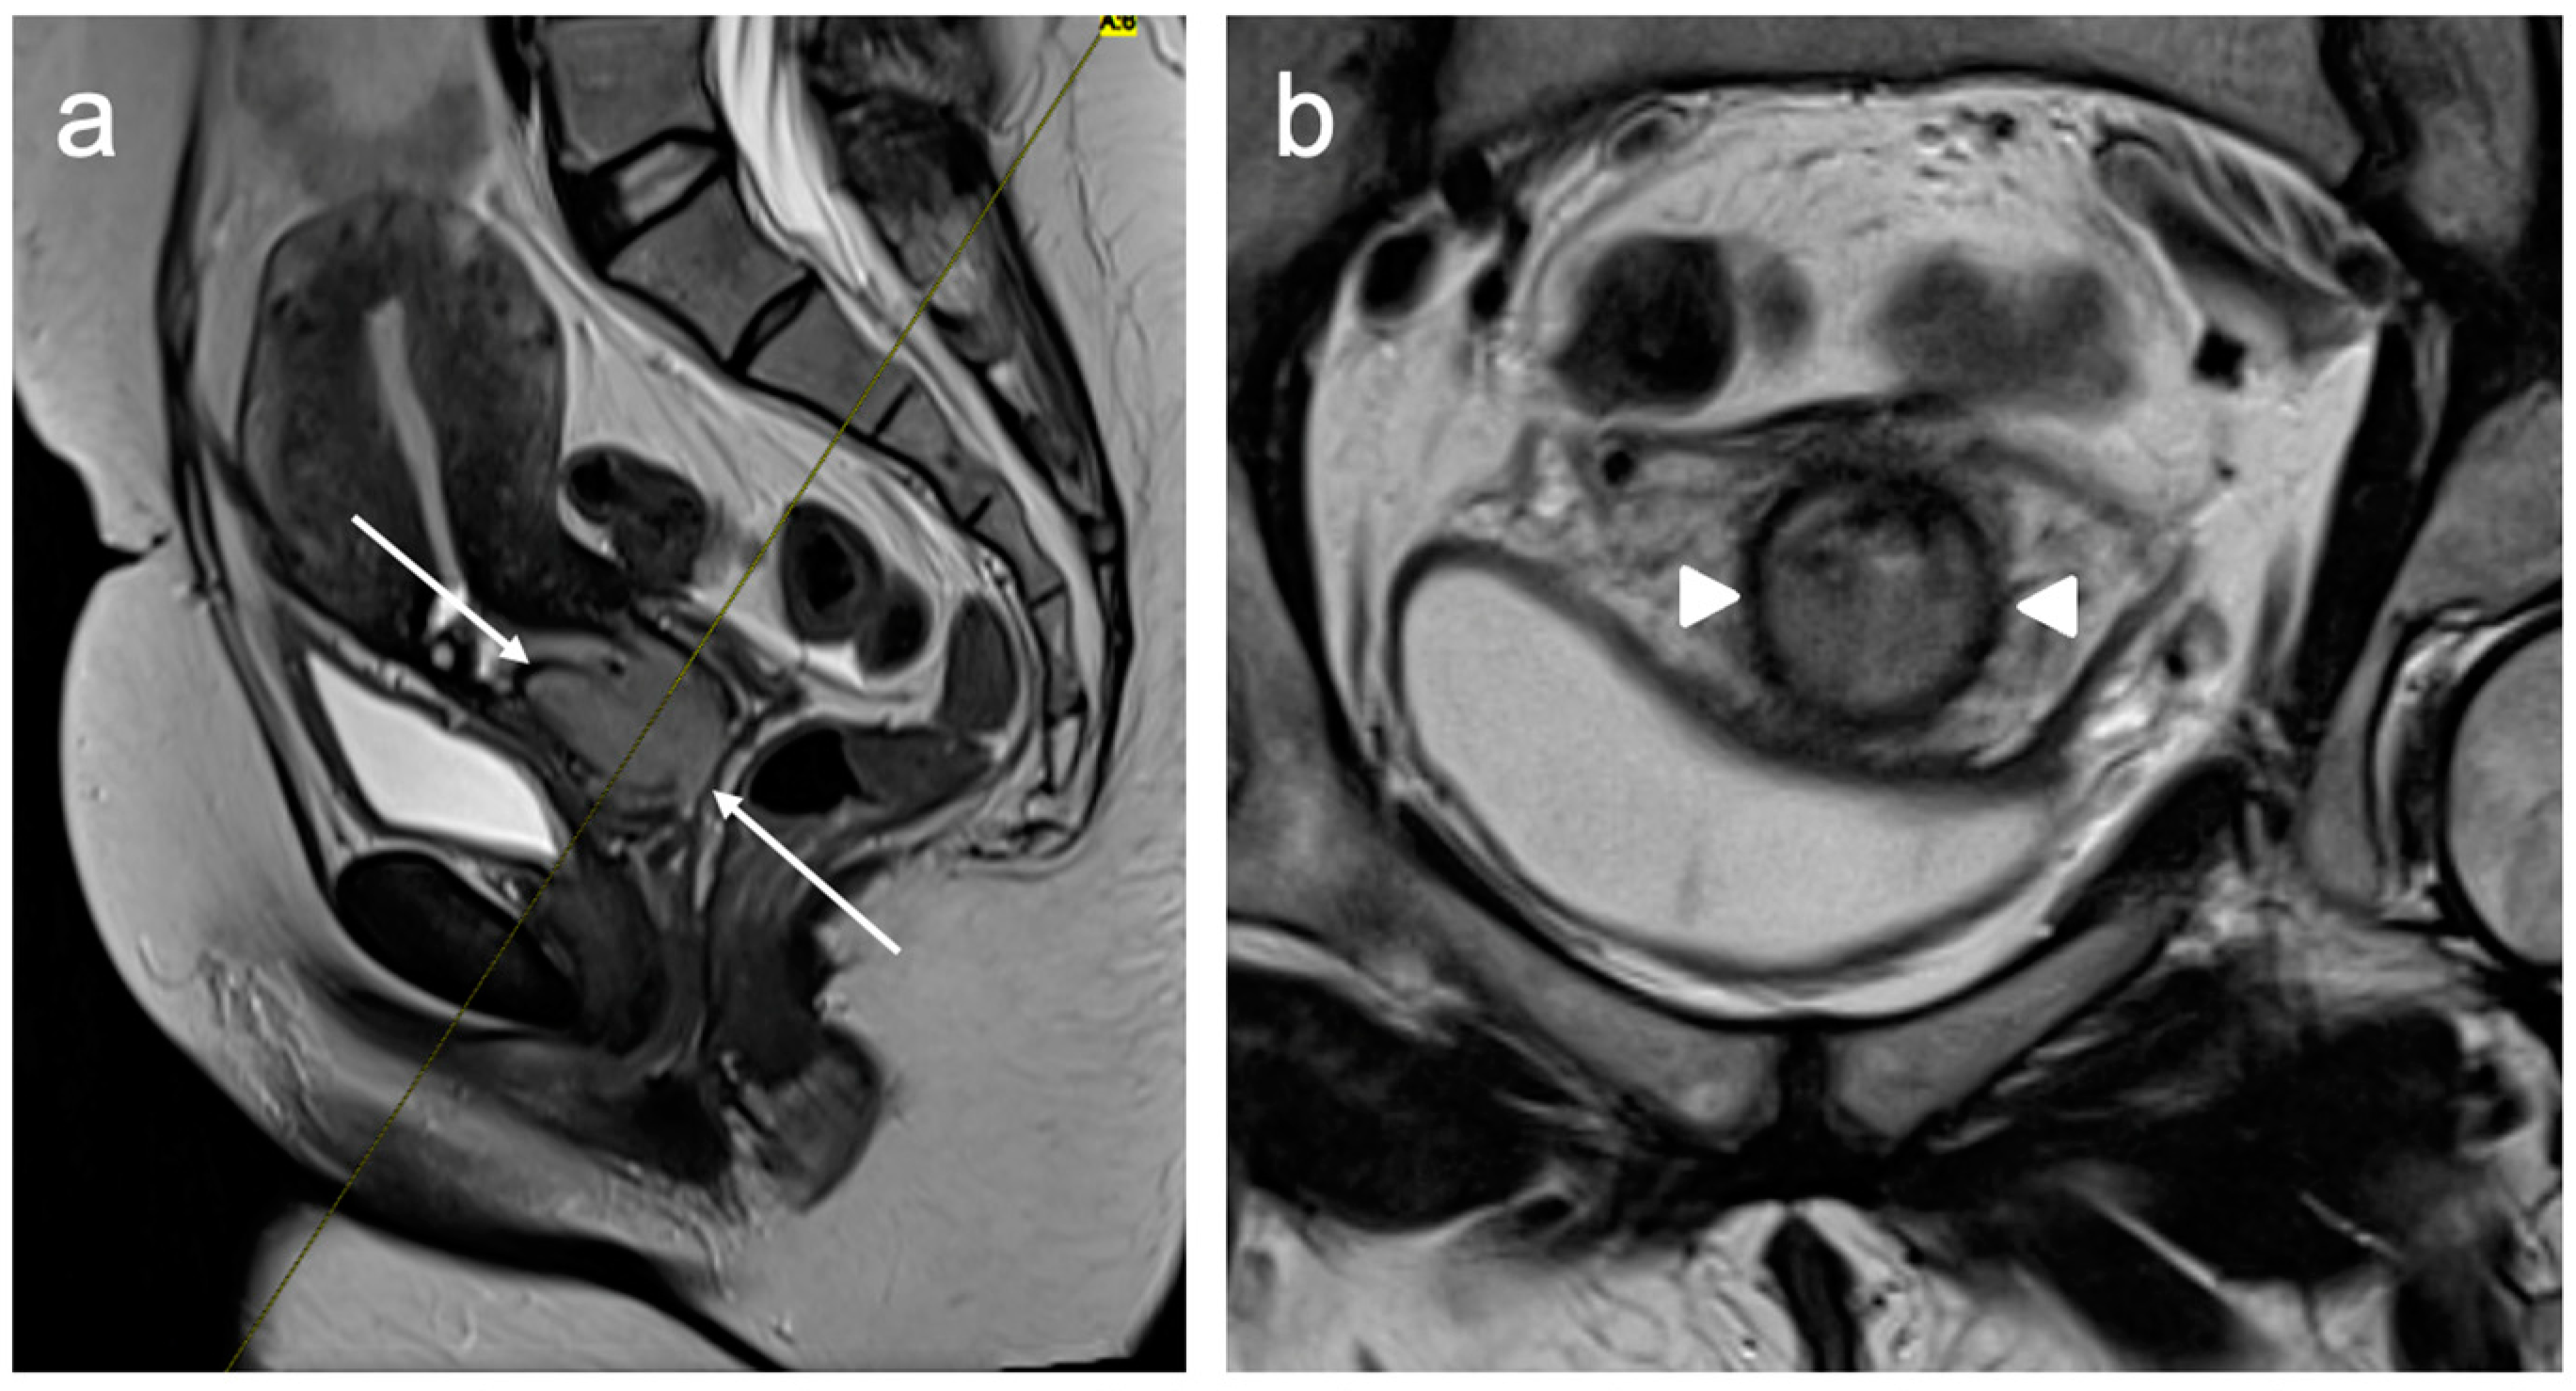

4. FIGO Stage I

5. FIGO Stage II

- McEvoy, S.H.; Nougaret, S.; Abu-Rustum, N.R.; Vargas, H.A.; Sadowski, E.A.; Menias, C.O.; Shitano, F.; Fujii, S.; Sosa, R.E.; Escalon, J.G.; et al. Fertility-sparing for young patients with gynecologic cancer: How MRI can guide patient selection prior to conservative management. Abdom. Radiol. 2017, 42, 2488–2512, Erratum in Abdom. Radiol. 2017, 42, 2966–2973. [Google Scholar]

- Halaska, M.; Robova, H.; Pluta, M.; Rob, L. The role of trachelectomy in cervical cancer. Ecancermedicalscience 2015, 9, 506. [Google Scholar] [CrossRef]

- Rockall, A.G.; Qureshi, M.; Papadopoulou, I.; Saso, S.; Butterfield, N.; Thomassin-Naggara, I.; Farthing, A.; Smith, J.R.; Bharwani, N. Role of Imaging in Fertility-sparing Treatment of Gynecologic Malignancies. Radiographics 2016, 36, 2214–2233. [Google Scholar] [CrossRef] [PubMed]

- Moro, F.; Bonanno, G.M.; Gui, B.; Scambia, G.; Testa, A.C. Imaging modalities in fertility preservation in patients with gynecologic cancers. Int. J. Gynecol. Cancer 2021, 31, 323–331. [Google Scholar] [CrossRef] [PubMed]

- Noël, P.; Dubé, M.; Plante, M.; St-Laurent, G. Early cervical carcinoma and fertility-sparing treatment options: MR imaging as a tool in patient selection and a follow-up modality. Radiographics 2014, 34, 1099–1119. [Google Scholar] [CrossRef] [PubMed]